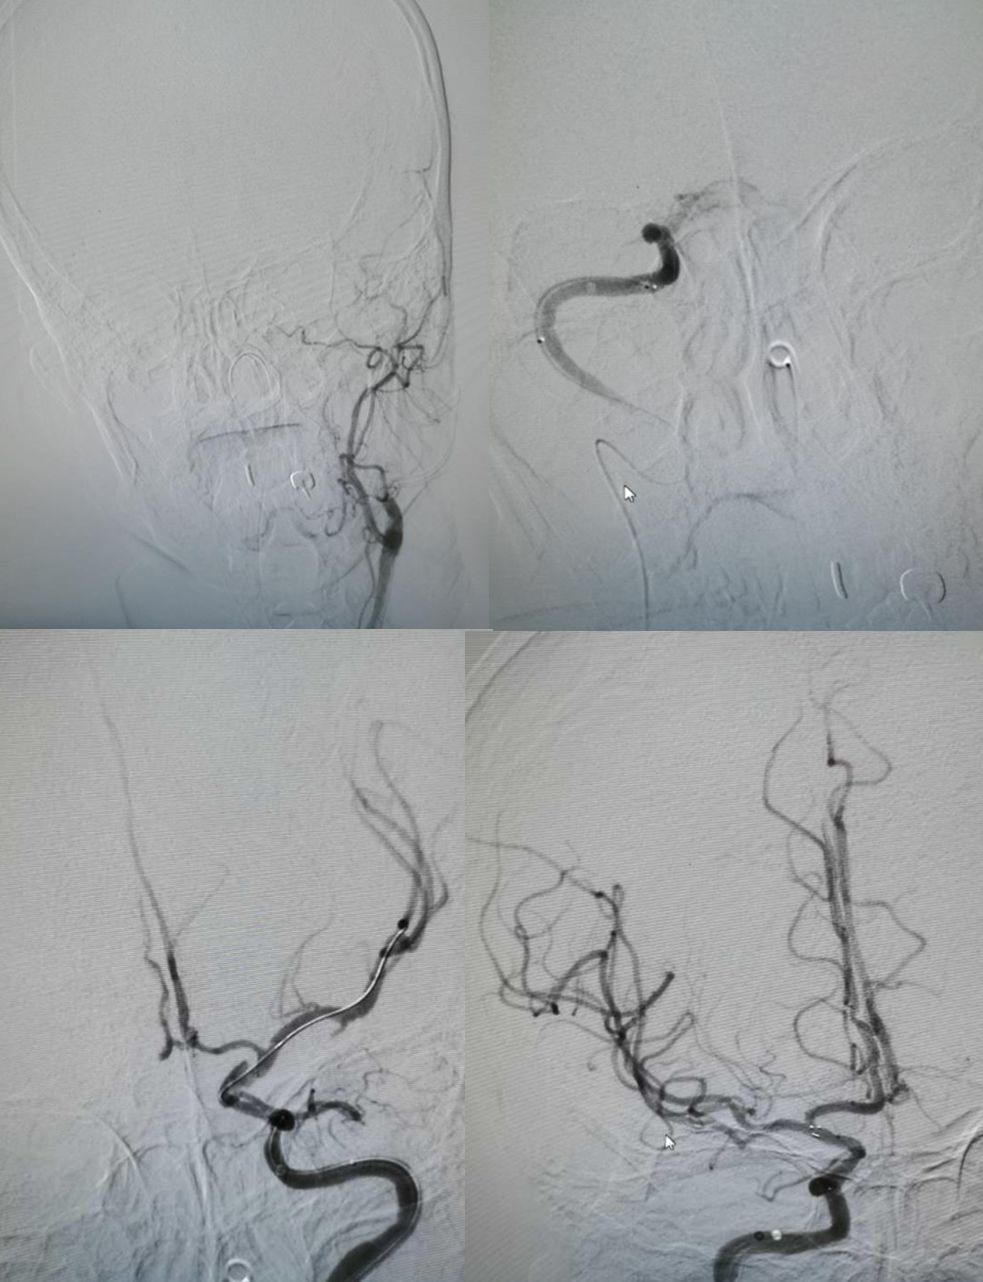

女,70岁,反复胸闷痛5年,头痛1周。

答案:大脑凸面蛛网膜下腔出血(cSAH)。其病因多样,如果年龄>60岁,临床反复发作性短暂性神经功能缺损症状,考虑脑动脉狭窄或闭塞(包括烟雾病)和CAA。如果临床<60岁,病程中伴有头痛,考虑静脉窦血栓、RCVS、PRES和血管炎。患者MRA如下图: